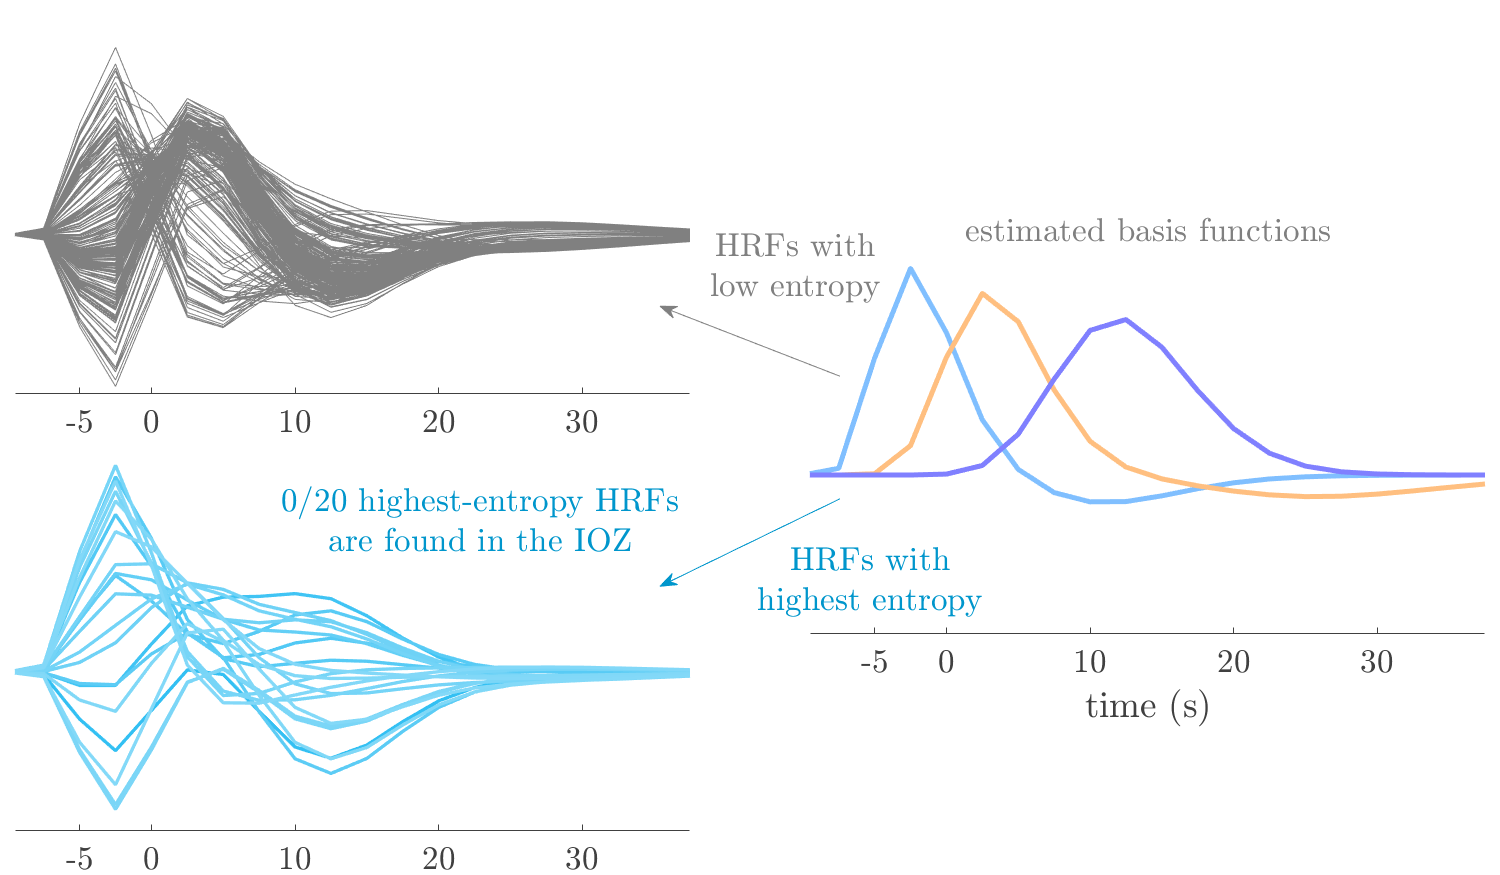

We analyze the solution with sources. Figure 1 shows the EEG signatures and HRF waveforms. One of the sources is highly correlated to the MWF reference (in grey), which was already known from Table B.3. This IED-related source had a typical low-frequency spectrum, which is expected for the typical spike-and-wave interictal discharges. The topography is relatively diffuse, although the highest amplitudes are mostly in the left hemisphere. This is in accordance with the lateralization of ictal onset zone (left temporal lobe, cfr. Table 1). There are some noteworthy observations to be made about some of the other components. The fourth has an unusually sharp spectrum, is mainly localized on two nonadjacent center electrodes, and is sustained for a single period of many seconds Hence, this component likely captured an artifact (of yet unknown origin), although we spotted no large-amplitude changes in the EEG itself. Similarly, the third source is only present at one frontal electrode, and exists in a frequency range above 20 Hz. It might represent a muscle artifact, e.g., due to frowning or twitching of some muscles in the forehead. The HRFs of all ROIs are shown in Figure 1(b). Two of the basis functions seem to have converged to a very similar waveform, which is an unfortunate possibility if two initial HRFs are too close to the same local optimum in their respective parameters. This reduces the expressive power of the basis set, which is clearly visible, since many ROIs have a nearly identical HRF. One of the twenty ROIs with the highest-entropy HRF overlapped the IOZ, although clearly this HRF (bold line) is not among the most dissimilar waveforms for this patient. This is also visible in Figure 2: both the HRF entropy and extremity maps show a small overlap with the delineated IOZ. Despite the good correspondence in the EEG domain, no significant (de)activation of the IED-component is found inside the IOZ.

We analyze the solution with sources, and show the results in Figure 3 and 4. As for patient 1, we found a source which is strongly correlated to the MWF envelope, and which had a mostly low-frequency behavior characteristic for spikes. The topography is mostly uninformative, and does not clearly correspond to the patient’s clinical data. The third source is mostly present at both sides of the head, is very sparsely active in time, and has a high-frequency content: this is most likely an artifact due to the neck muscles. Again, there is one of the highest-entropy HRFs which belongs to a ROI in the IOZ. Now, the waveform is clearly resolved from the other HRFs, through the strong initial dip (before 0 seconds). Such a dip is sometimes observed in HRFs, but its underlying physiological mechanism is not yet fully understood. It is possible that this dip reflects altered vascular autoregulation near the IOZ (cfr. the explanation in the Section 1 of the main text), or a rapid depletion in oxygen due to IED generation (before the IED becomes visible on the EEG). Figure 4 furthermore shows that the IED-related component is significantly active in parts of the IOZ, and deactive in others. As mentioned earlier, this deactivation may or may not be due to errors in sign correction. Interestingly, the ROI with the high alteration in neurovascular coupling is distinct from both the activated and deactivated ROIs.

We analyzed the solution with sources, and show the results in Figure 5 and 6. There is one source which is mostly correlated to the reference (but not extremely, see also Table B.3). This source had a right-temporal focus, conform the diagnosis in Table 1. The second source illustrates the phenomenon of an erroneous sign exchange between the spatial and spectral profiles. Also one of the HRFs has a negative polarity, which is a failure of the sign correction procedure (in this case, because there is exceptionally no positive overshoot). However, the HRF variability metrics are still interpretable, and indeed two ROIs among the ones with the highest-entropy HRFs overlap with the IOZ. The IED component is significantly active in a tiny portion of the IOZ (cfr. Figure 6). The second source is significantly active in symmetrical parts of the parietal lobe. Given its ongoing fluctuation over time, we hypothesize that this source captures a resting state network (RSN).

We analyze the solution with sources, and show the results in Figure 7 and 8. There is a clear IED-related component, with a very high correlation to the MWF reference, a typical spectrum, and an anterior-temporal focus, which corresponds very well to the patient’s diagnosis (cfr. Table 1). The fifth source seems present at only one channel, and has spectral harmonic at Hz and Hz. One of these peaks is reminiscent of the fourth component in patient 1. As Figure 8 shows, the HRF entropy and extremity prove to be strong biomarkers for the IOZ in this case, and also the significant IED activation and deactivation allow correct localization. In Figure 7, it is clear that some HRFs may still have the wrong sign, which means that the interpretation of ‘active’ and ‘deactivated’ is flipped in those ROIs. Hence, regions of significant deactivation are in fact significantly activated. The fourth source had a significant overlap with the auditory RSN, and its spectrum reveals activity in the band.

We analyze the solution with sources, and show the results in Figure 9 and 10. One source is strongly correlated to the MWF, while the other source is likely an artifact, given its very sparse temporal profile. Both sources coincide at one high-amplitude peak, by which we infer that this is probably an artifactual period in the signal. Indeed, when inspecting the original EEG signals, we found high-frequency muscle artifacts at these times. This source also had no significant activation in its spatial map, which corroborates its non-neuronal origin. The IED-related source had a broader spectrum than most other cases, and an uninformative topography. None of the ROIs with high-entropy HRFs is located in the IOZ. The pseudo t-map provides correct localization of the IOZ, however.

We analyze the solution with sources, and show the results in Figure 11 and 12. We found a clear IED-related component, with a characteristic spectrum and a topography which is backed up by the patient’s diagnosis (left anterior-temporal IOZ). The fourth source has a very similar topography and spectrum to the fifth source in patient 5. One HRF inside the IOZ had a high-entropy, and is distinguishable from the others by its very sluggish waveform, i.e., it is smeared out in time, with no sharp over- or undershoot. Also the pseudo t-map provided an accurate localization of the IOZ. Notably, in this patient, the extremity metric misses the deviating HRF in the IOZ (while the entropy metric picks it up). The second source overlapped with the frontal part of the default mode network (DMN), and is active in the and low bands.

We analyze the solution with sources, and show the results in Figure 13 and 14. We found two components which had correlated time courses. At the time of the peaks, we found higher-amplitude events in the EEG with dubious origin, hence they may or may not be artifacts. One of both components is more strongly correlated to the MWF, and its activation is concordant with the IOZ. The second component shows high overlap with the sensorimotor network. For this patient, none of the IOZ’s ROIs had extreme values of either HRF metric.

We analyze the solution with sources, and show the results in Figure 15 and 16. In this patient, there is only a moderate correlation of a component with the MWF reference time course. This component’s topography (left occipital) agrees with the clinical description, however. The HRF extremity (and not the entropy) is high in a small part of the IOZ. Both the significant IED activation and deactivation allow correct localization as well. The second source seemingly captured high-frequency oscillatory activity in the sensorimotor network, similar to the previous patient.

We analyze the solution with sources, and show the results in Figure 17 and 18. The IED-related source had a high correlation with the MWF reference, but an odd bimodal spectrum. Its EEG topography is very consistent with the clinical description. Both HRF extremity and entropy are useful biomarkers for the IOZ. The IED activation and deactivation maps each had a very small overlap with the IOZ. The second source is temporally sparse and captures high-frequency EEG variations, which we identified as muscle artifacts.

We analyze the solution with sources, and show the results in Figure 19 and 20. Again we observe an IED-related source and a seemingly artifactual source with a spectral peak near 34 Hz. Many of the high-entropy HRFs are highly noncausal, and are associated to ROIs inside the IOZ. Hence, with both HRF metrics, the highest-scoring ROIs provides good localization of the HRF. While there are no significantly active ROIs in the IOZ, there are several significantly deactivated ROIs, which may indicate that the sign standardization was not done flawlessly (cfr. also some of the negative-peaking HRFs for patient 10). Surprisingly, the second source had one significantly active ROI, which overlaps with the IOZ, but which did not match its EEG topography. Hence, the nature of this source remains ambiguous.